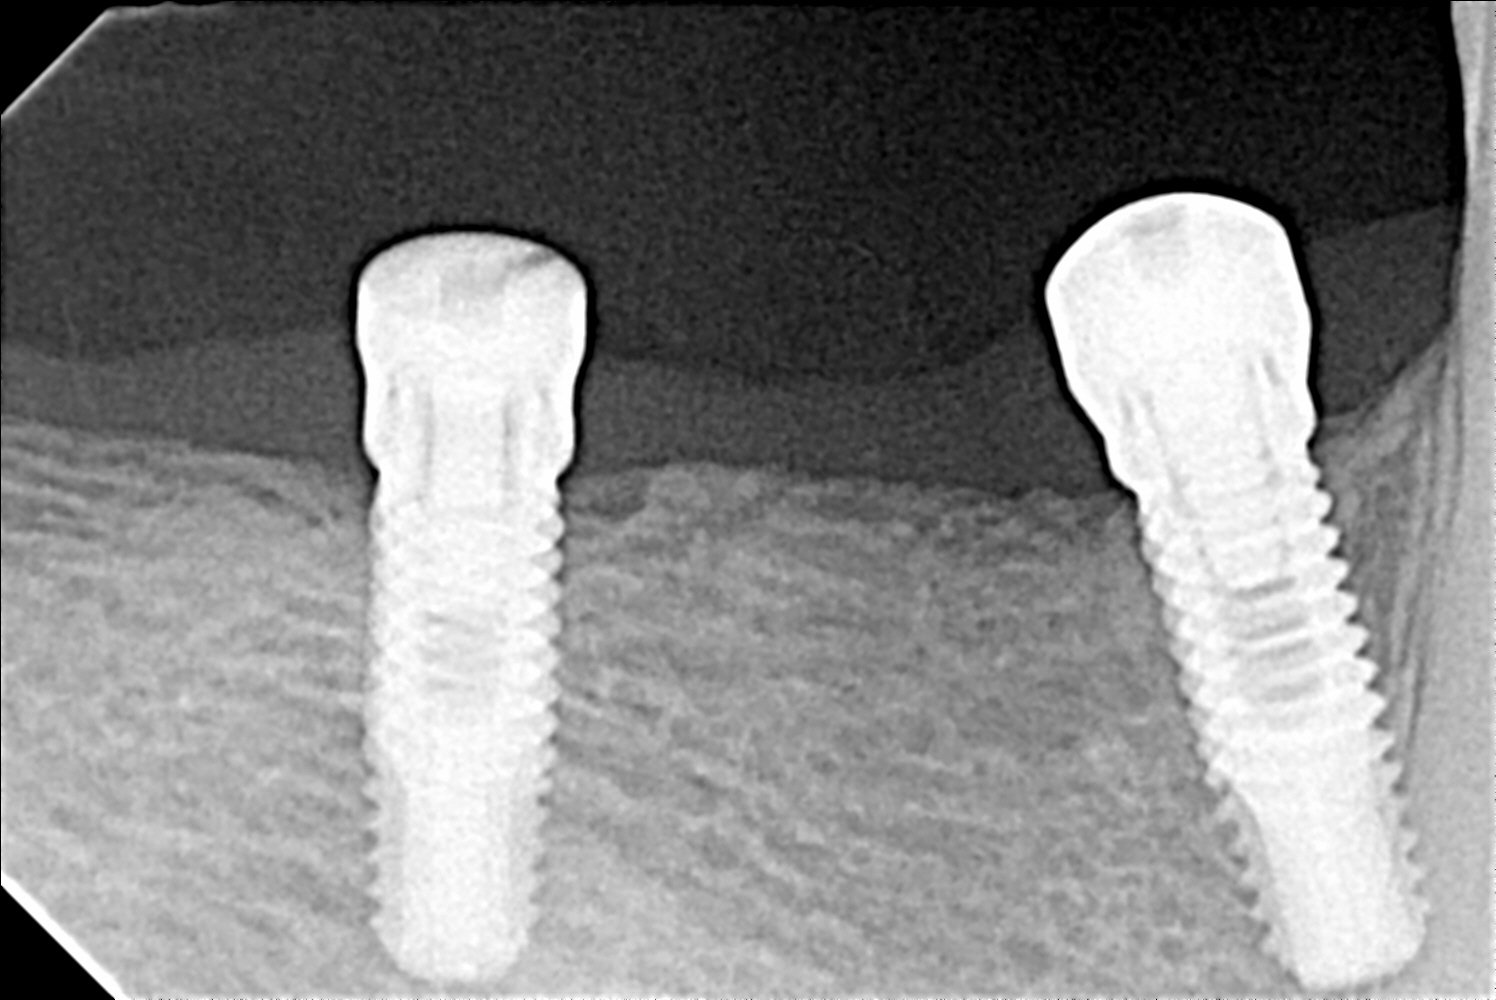

implantes en 4 cuadrante

Paciente de Idental que ha llegado a nuestra consulta. Colocados hace 2 o 3 años en Madrid